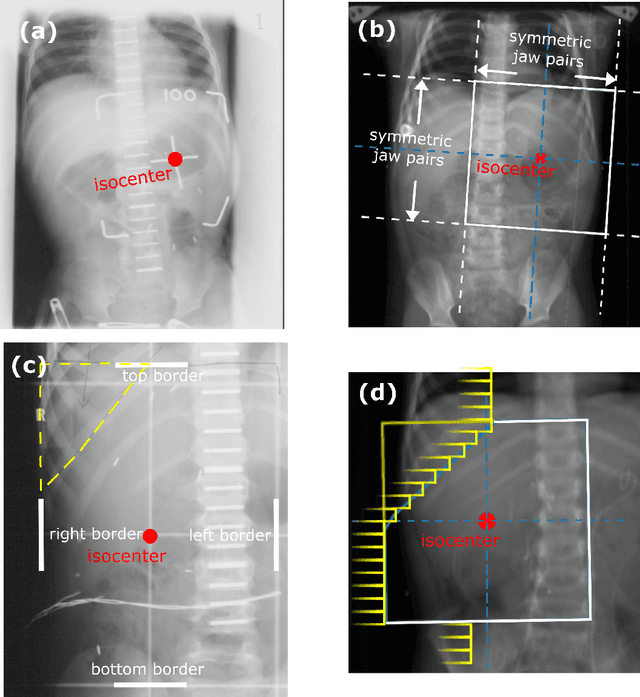

Abstract:To study radiotherapy-related adverse effects, detailed dose information (3D distribution) is needed for accurate dose-effect modeling. For childhood cancer survivors who underwent radiotherapy in the pre-CT era, only 2D radiographs were acquired, thus 3D dose distributions must be reconstructed. State-of-the-art methods achieve this by using 3D surrogate anatomies. These can however lack personalization and lead to coarse reconstructions. We present and validate a surrogate-free dose reconstruction method based on Machine Learning (ML). Abdominal planning CTs (n=142) of recently-treated childhood cancer patients were gathered, their organs at risk were segmented, and 300 artificial Wilms' tumor plans were sampled automatically. Each artificial plan was automatically emulated on the 142 CTs, resulting in 42,600 3D dose distributions from which dose-volume metrics were derived. Anatomical features were extracted from digitally reconstructed radiographs simulated from the CTs to resemble historical radiographs. Further, patient and radiotherapy plan features typically available from historical treatment records were collected. An evolutionary ML algorithm was then used to link features to dose-volume metrics. Besides 5-fold cross validation, a further evaluation was done on an independent dataset of five CTs each associated with two clinical plans. Cross-validation resulted in mean absolute errors $\leq$0.6 Gy for organs completely inside or outside the field. For organs positioned at the edge of the field, mean absolute errors $\leq$1.7 Gy for $D_{mean}$, $\leq$2.9 Gy for $D_{2cc}$, and $\leq$13% for $V_{5Gy}$ and $V_{10Gy}$, were obtained, without systematic bias. Similar results were found for the independent dataset. To conclude, our novel organ dose reconstruction method is not only accurate, but also efficient, as the setup of a surrogate is no longer needed.